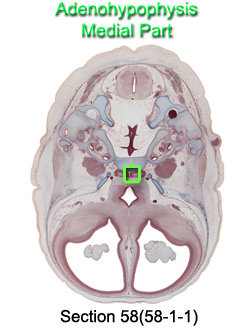

Adenohypophysis Medial Part

Carnegie Embryo #9226

58-01-01